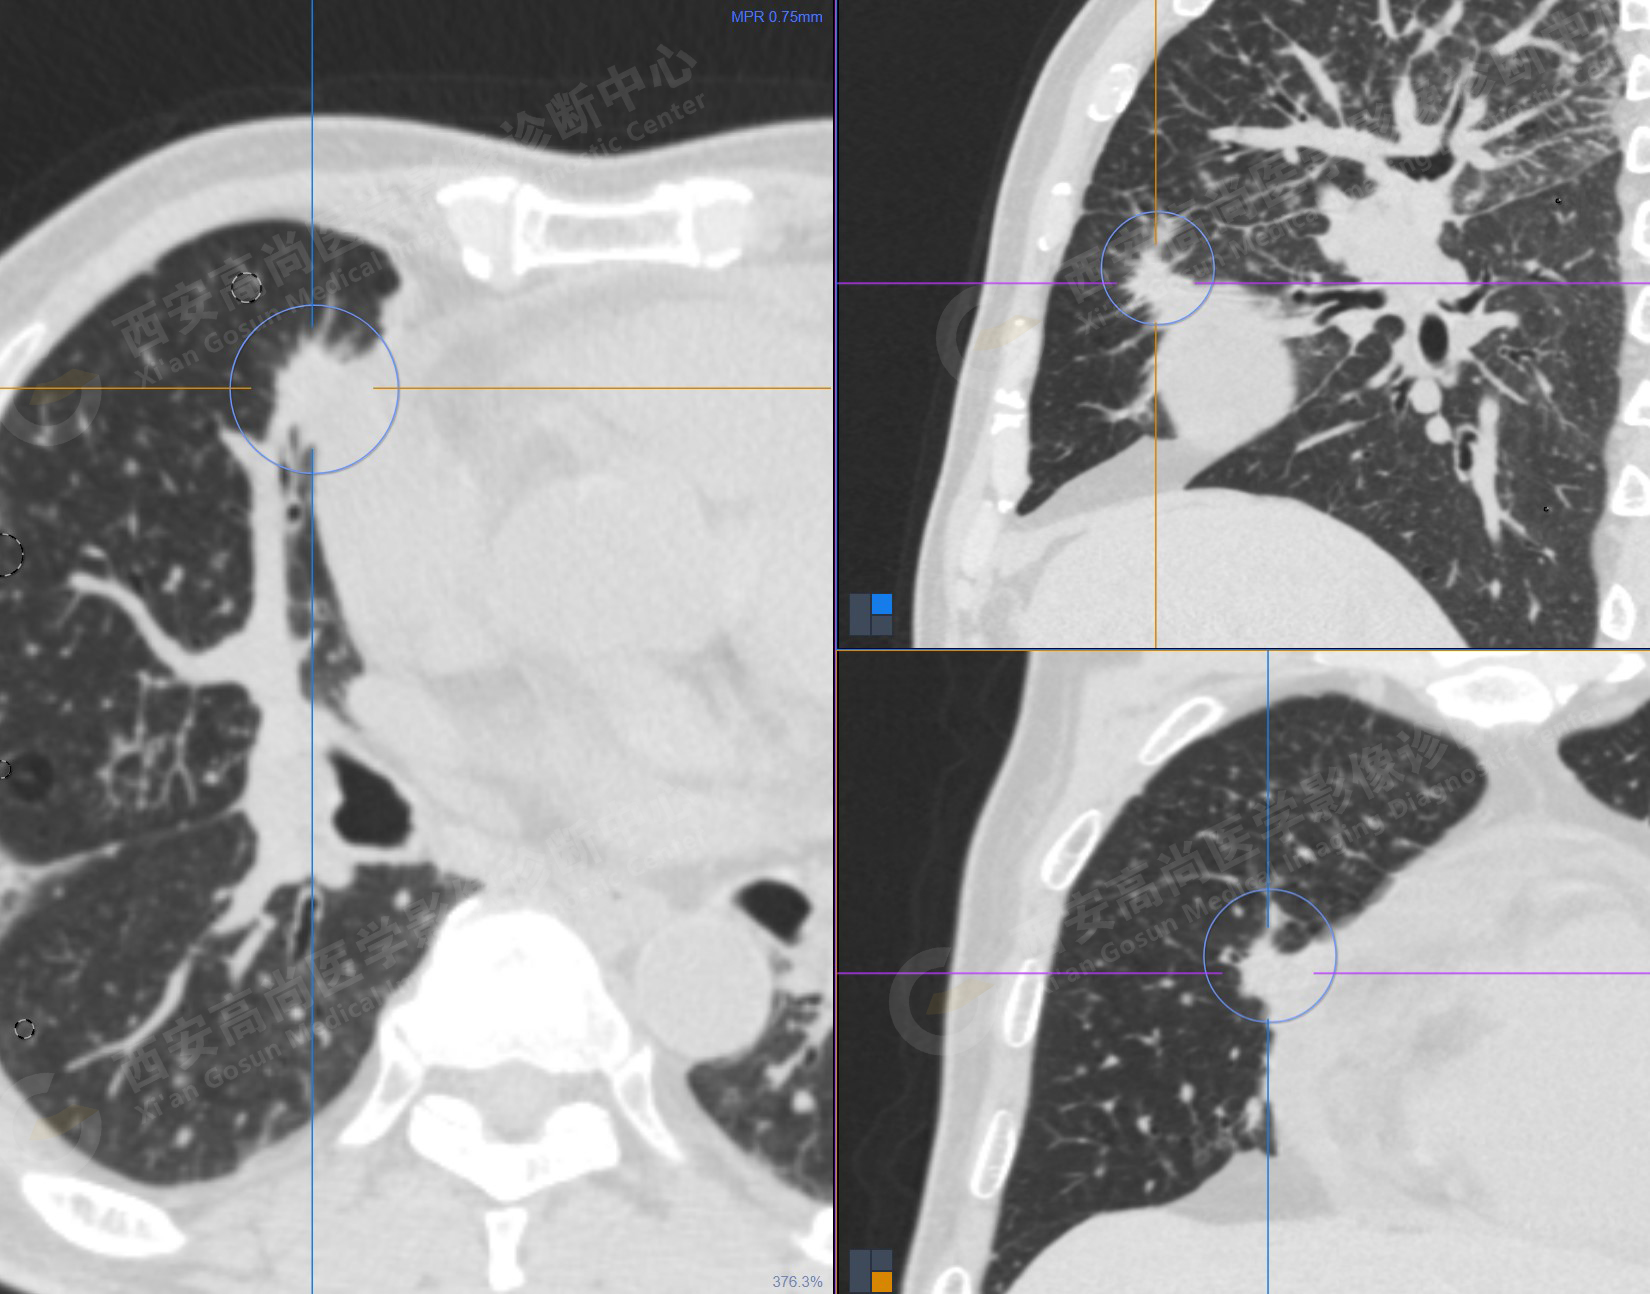

1.以下為肺內(nèi)原發(fā)灶

1.右肺中葉內(nèi)側段軟組織結節(jié),呈淺分葉狀,邊緣可見毛刺及胸膜牽拉征,呈FDG代謝異常增高,考慮為周圍型肺癌。